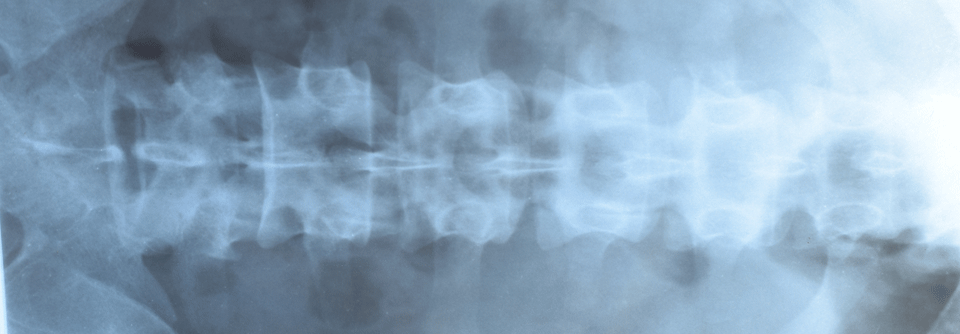

Spondyloarthritis: Nächtlicher Aufwachschmerz im Rücken

Einer Ihrer jüngeren Patienten wacht nachts wegen Rückenschmerzen auf. Vorsicht, sie könnten das erste Zeichen einer Spondyloarthritis sein. Eine…

Rheumatologie DGIM 2021